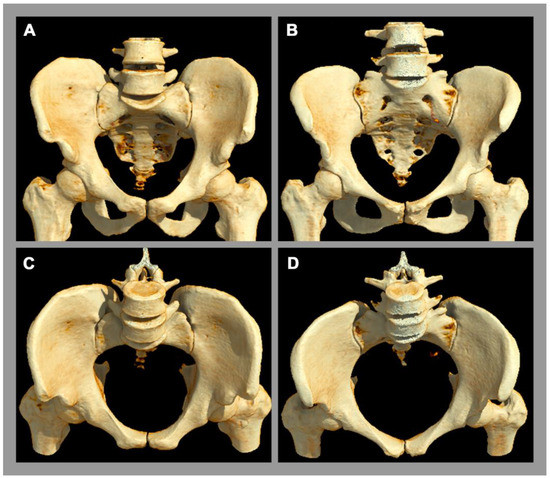

There is a well-established sexual dimorphism of the SIJ with consecutively more degenerative or mechanical stress-induced disease in the female SIJ [2]. In women, the ligaments of the SIJ are more flexible and the center of gravity is more ventrally located [8]. In the male pelvis, especially the inter-cristal measurement is larger than in the female pelvis [2]. The articular facet at the base of the sacrum for the 5th lumbar vertebra occupies more than one-third of the width of the base of the sacrum in males [2]. In females, this corresponds to less than one-third, whose sacrum is relatively wider [2]. In addition, the pelvic cavity is longer and more conically configured in males, whereas the female pelvic cavity is shorter and more cylindrical orientated [2], see Figure 2.

Figure 2.

Anatomy of the pelvis. A 3D computed tomography reconstruction. (A,C) Male pelvis. (B,D) Female pelvis. There is obvious sexual diamorphism in the pelvic anatomy. The male pelvic cavity is longer and more conically configurated with a longer and narrower sacrum, while the female pelvic cavity is narrower and cylindrically orientated.